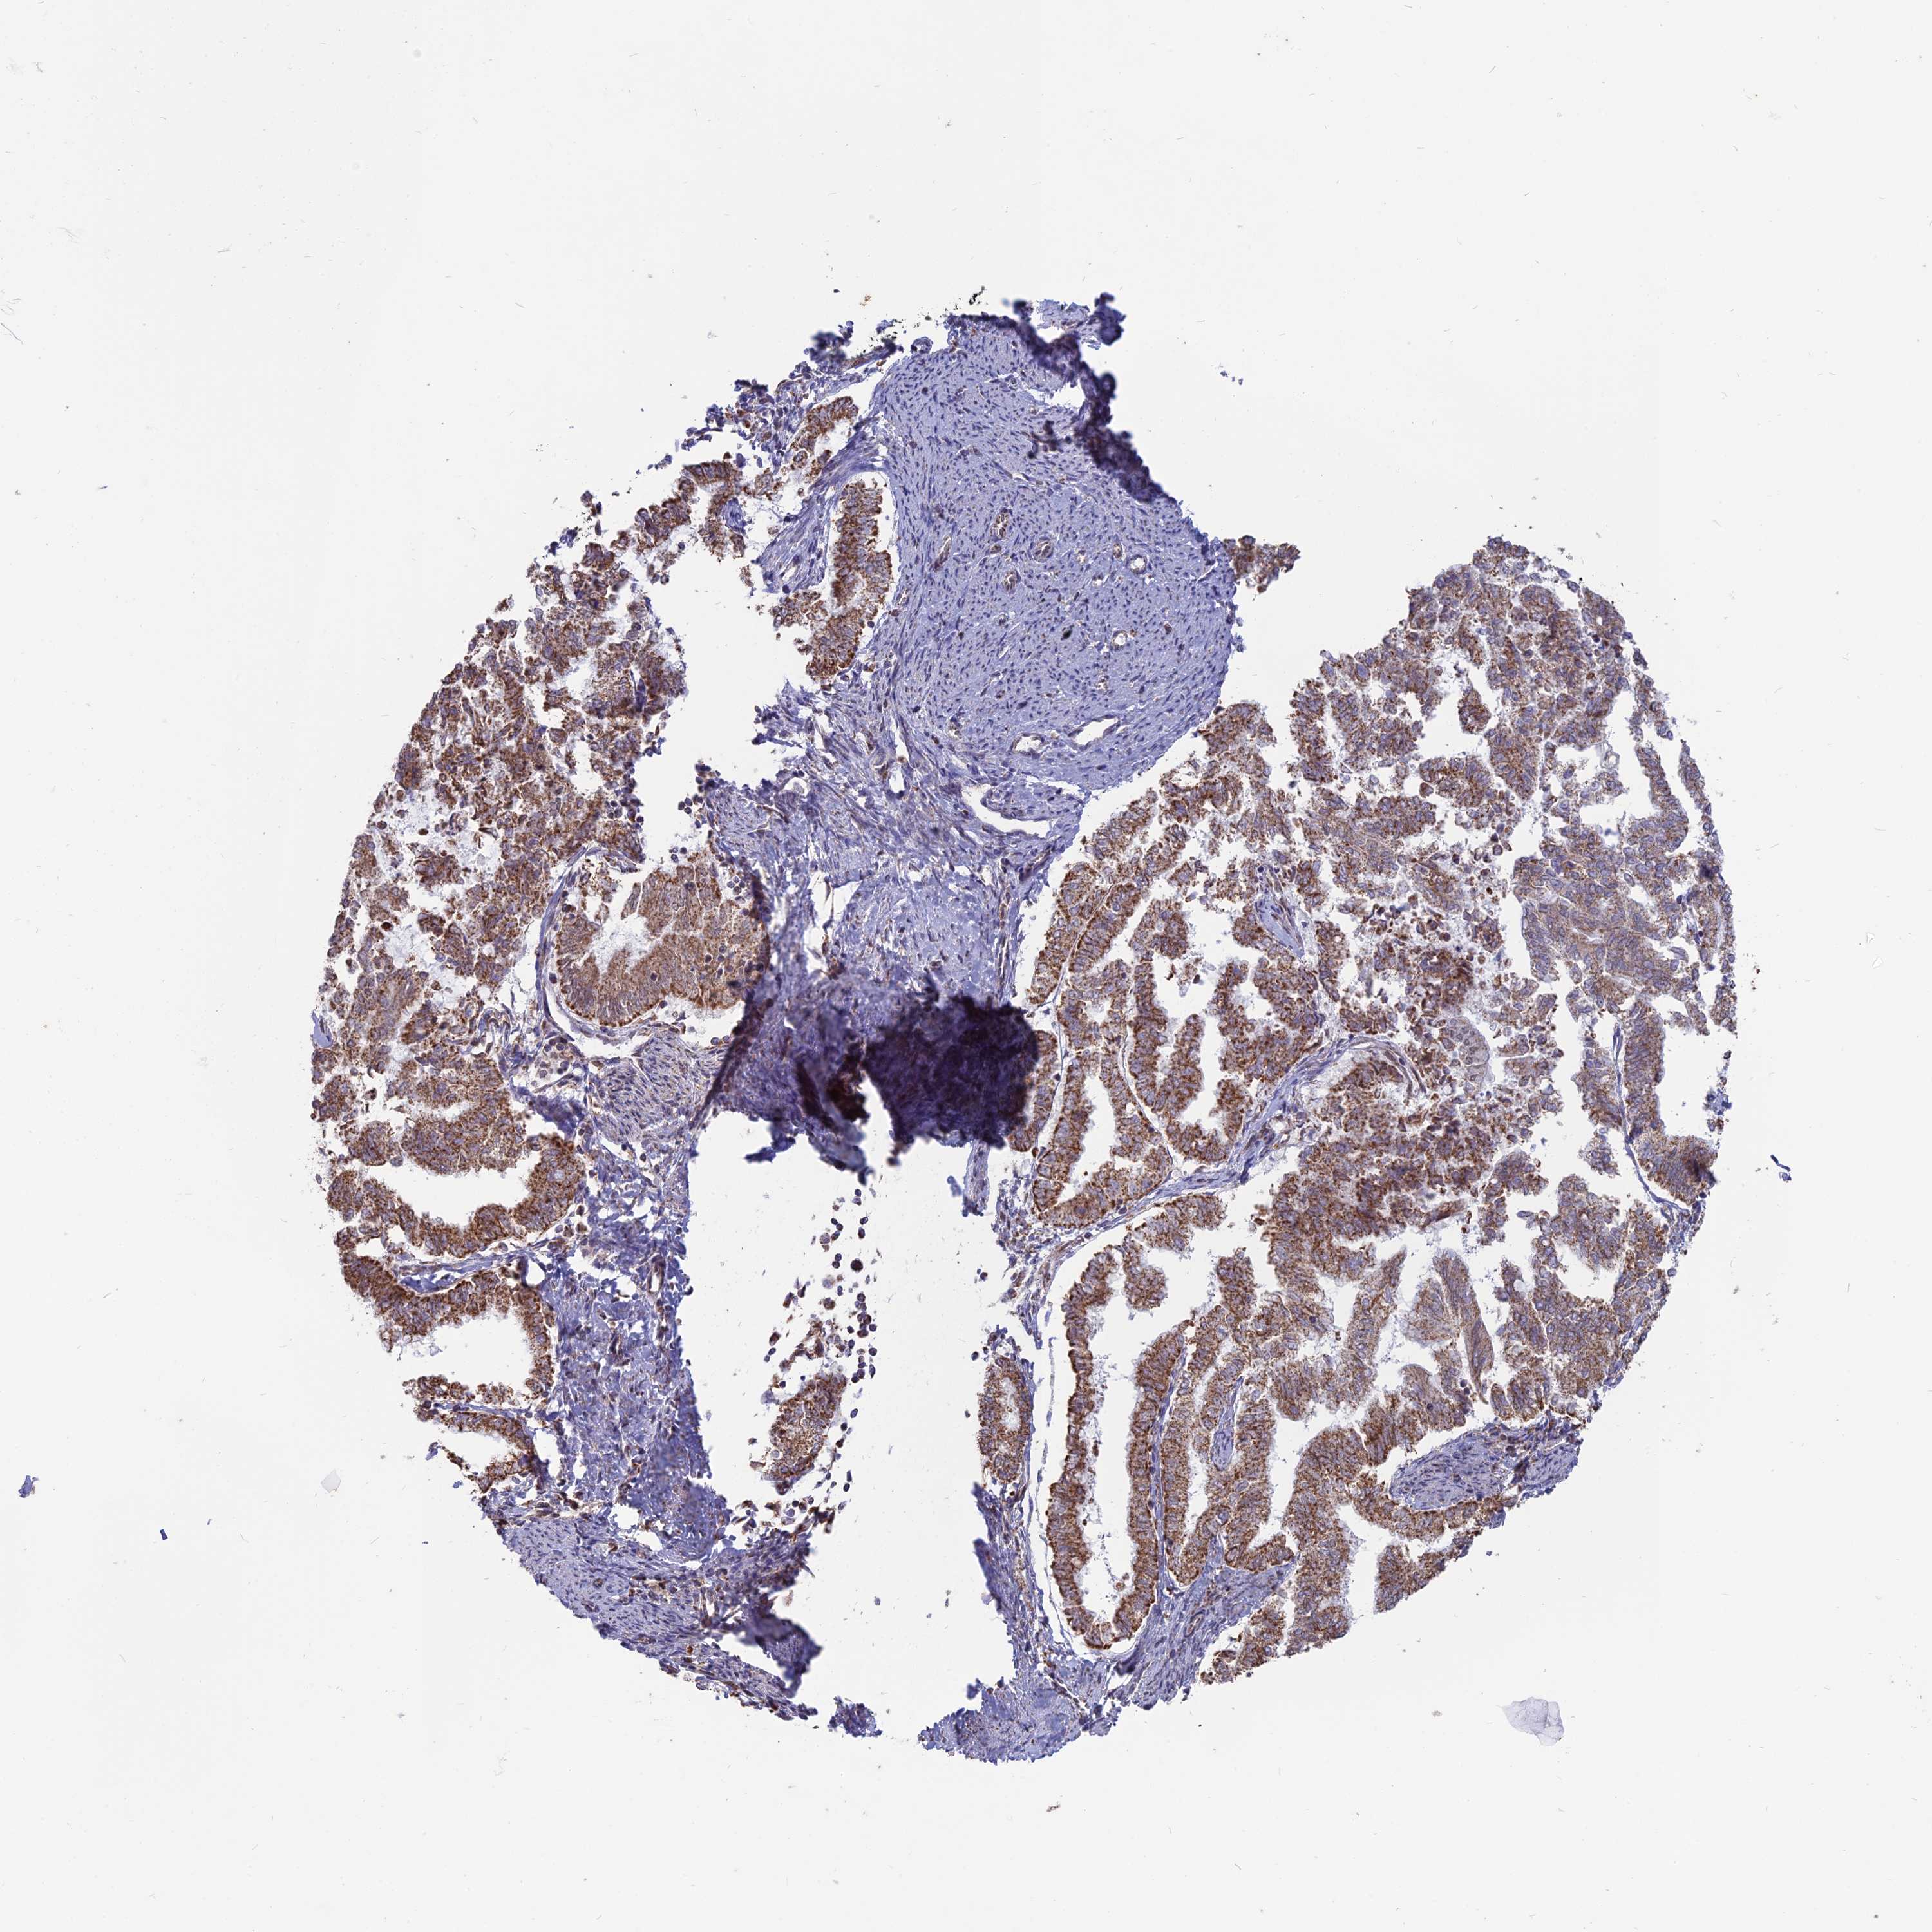

ENDOMETRIAL CANCER - Protein expressioni

A mouse-over function shows sample information and annotation data. Click on an image to view it in a full screen mode. Samples can be filtered based on level of antibody staining by selecting one or several of the following categories: high, medium, low and not detected. The assay and annotation is described here.

Note that samples used for immunohistochemistry by the Human Protein Atlas do not correspond to samples in the TCGA dataset.

Antibody stainingi

Antibody staining in the annotated cell types in the current human tissue is reported as not detected, low, medium, or high, based on conventional immunohistochemistry profiling in selected tissues. This score is based on the combination of the staining intensity and fraction of stained cells.

Each image is clickable and will lead to virtual microscopy that enables deeper exploration of all samples and also displays staining intensity scores, fraction scores and subcellular localization as well as patient and tissue information for each sample.

Antibody HPA042636

Antibody HPA042840

Staining

High

Medium

Low

Not detected

Intensity

Strong

Moderate

Weak

Negative

Quantity

>75%

75%-25%

<25%

None

Location

Nuclear

Cytoplasmic/membranous

Cytoplasmic/membranous,nuclear

Adenocarcinoma, NOS